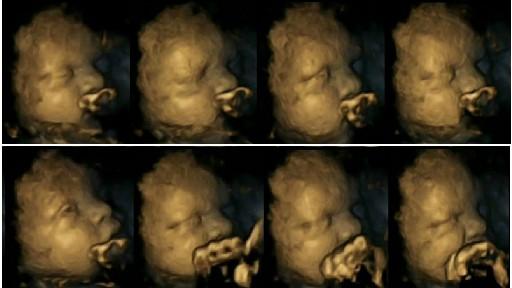

Un studiu recent, realizat pe 20 de viitoare mămici, dintre care patru erau fumătoare, arată că fetuşii reacţionează diferit în cazul în care mama lor fumează sau nu.

În cazul în care mama este dependentă de tutun, fătul încearcă să se apere, ducând mâinile la gură, nas, şi cap.

Dr Nadja Reissland, care a realizat mai multe ecografii 4D mămicilor implicate în studiu, a declarat că efectele tutunului asupra fătului sunt extrem de nocive, ducând până la naşterea copilului cu un mic grad de retard, alergii sau rezistenţa la anumite substanţe.